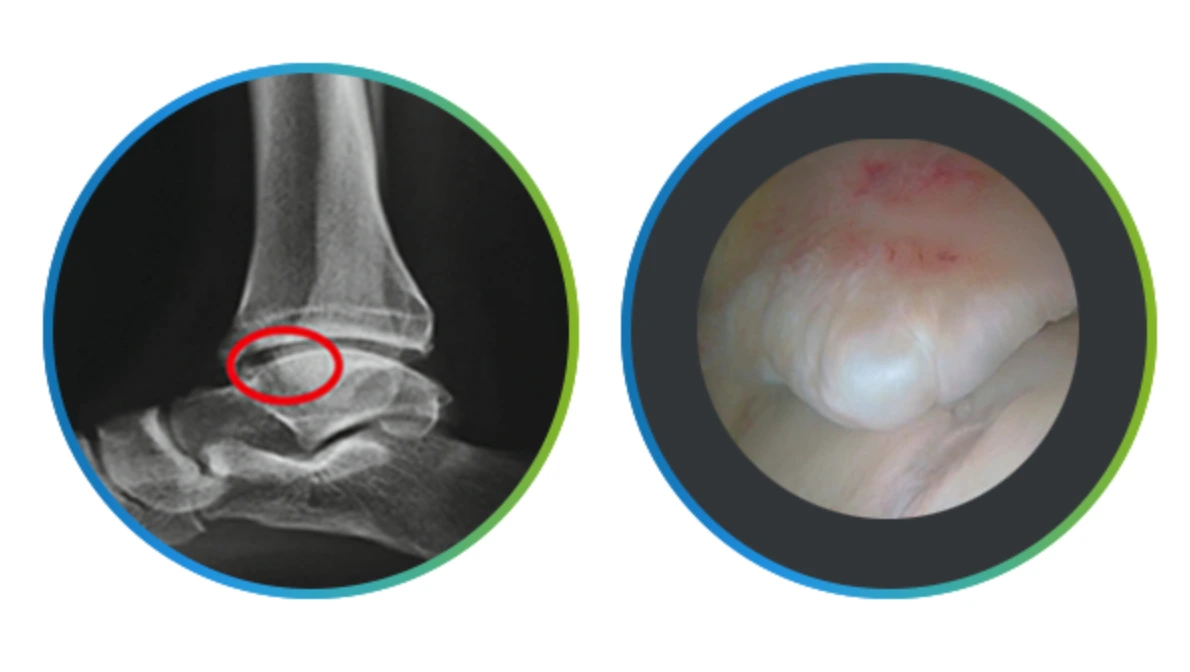

에이스병원에서는 발목통증으로 병원을 찾은 환자들의 발목상태를 정확히 알기 위해 X-ray로 일단 인대의 상태를 확인하는데요.

이후 얼마나 자주 발목을 삐었는지, 통증의 정도는 어떤 지, 원인이 무엇인지 등을 문진한 후에 필요하다면 MRI로 보다 정확한 연골선상과 골극변형 등을 확인하게 되지요.

이렇게 확인을 하고 나면 환자의 상황에 맞춰 약물치료, 주사치료, 물리치료는 물론 필요하다면 관절내시경을 사용한 수술 등도 고려해야 합니다.